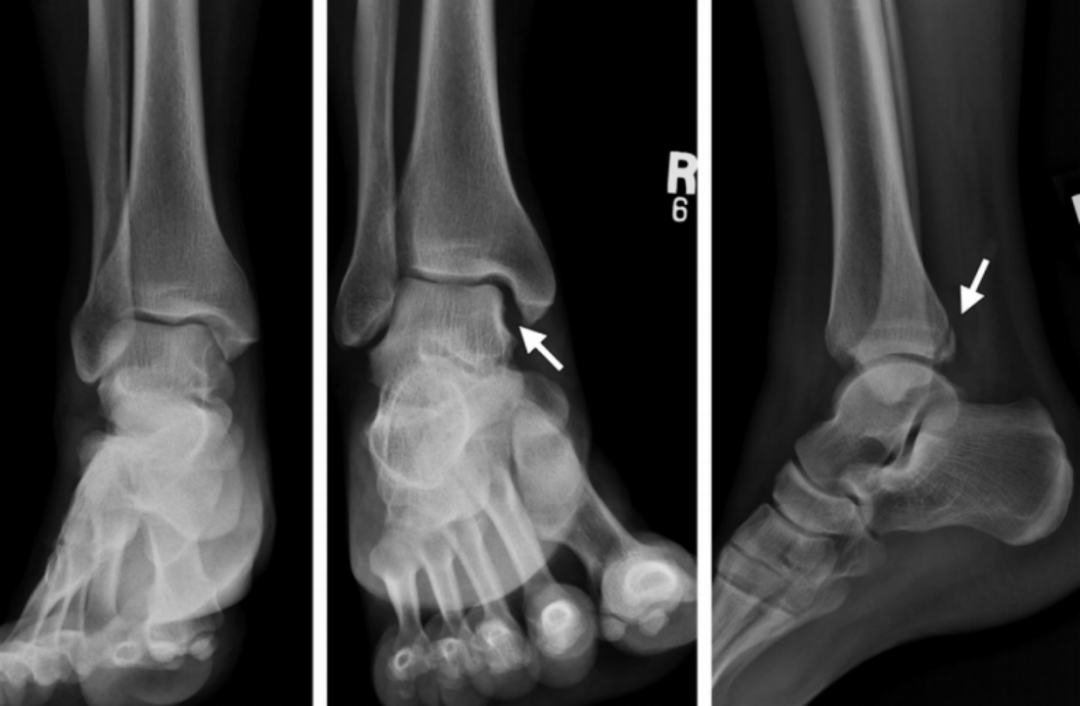

3、旋前(外翻)外旋损伤(简称 PE)

伤足处于旋前位,距骨外旋,三角韧带首先被拉紧。

旋前外旋损伤

I 度:首先发生的是三角韧带的断裂或者内踝的撕脱骨折。

I 度损伤 X 线显示:内踝水平骨折;侧位 X 线片显示后踝完整。这种损伤与旋前外展 I 度非常相似。

Ⅱ 度:距骨外旋力量继续作用于下胫腓关节,下胫腓前韧带和骨间韧带或韧带附着点撕脱骨折。

II 度损伤 X 线显示:内踝间隙增宽,提示三角韧带断裂;胫腓骨间隙增宽,提示下胫腓前联合断裂。

Ⅲ 度:腓骨骨折发生于胫骨远端关节面以上水平,甚至可以位于腓骨近端即 Maisonneuve 骨折,骨折线从前上方斜向后下方,即与旋后(内翻)外旋骨折相反。

III 度损伤 X 线片显示:内踝骨折和腓骨近端螺旋形骨折;胫腓骨间隙增宽;侧位片显示腓骨骨折,后踝无骨折。

Ⅳ 度:最后发生下胫腓后韧带断裂,或其胫骨附着点的撕脱骨折(Volkmann 骨折块)。

IV 度损伤 X 线片显示:内踝骨折;胫腓骨间隙增宽,提示下胫腓联合断裂,腓骨骨折位于下胫腓联合水平上;侧位片显示胫骨向前移位和后踝撕脱骨折。